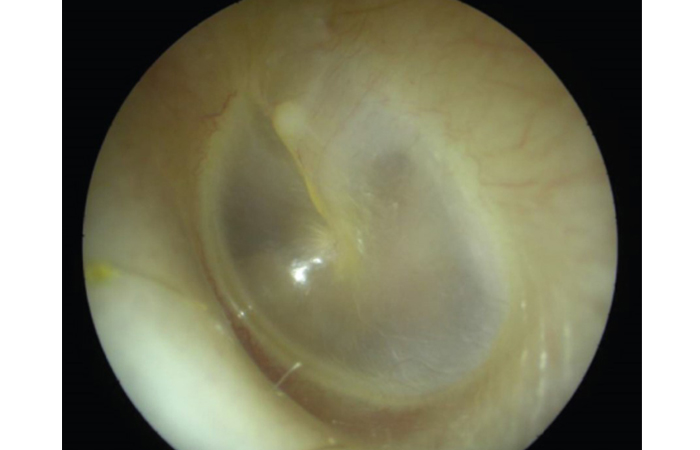

A normal eardrum (Figure 1) is translucent and greyish in colour. Acute otitis media causes inflammation of the eardrum (Figure 2).

Left normal ear drum.

Source: ABC of Ear, Nose and Throat edited by Harold Ludman, Patrick J. Bradley. 6th ed, 2013. Wiley. Reproduced with permission of Wiley.